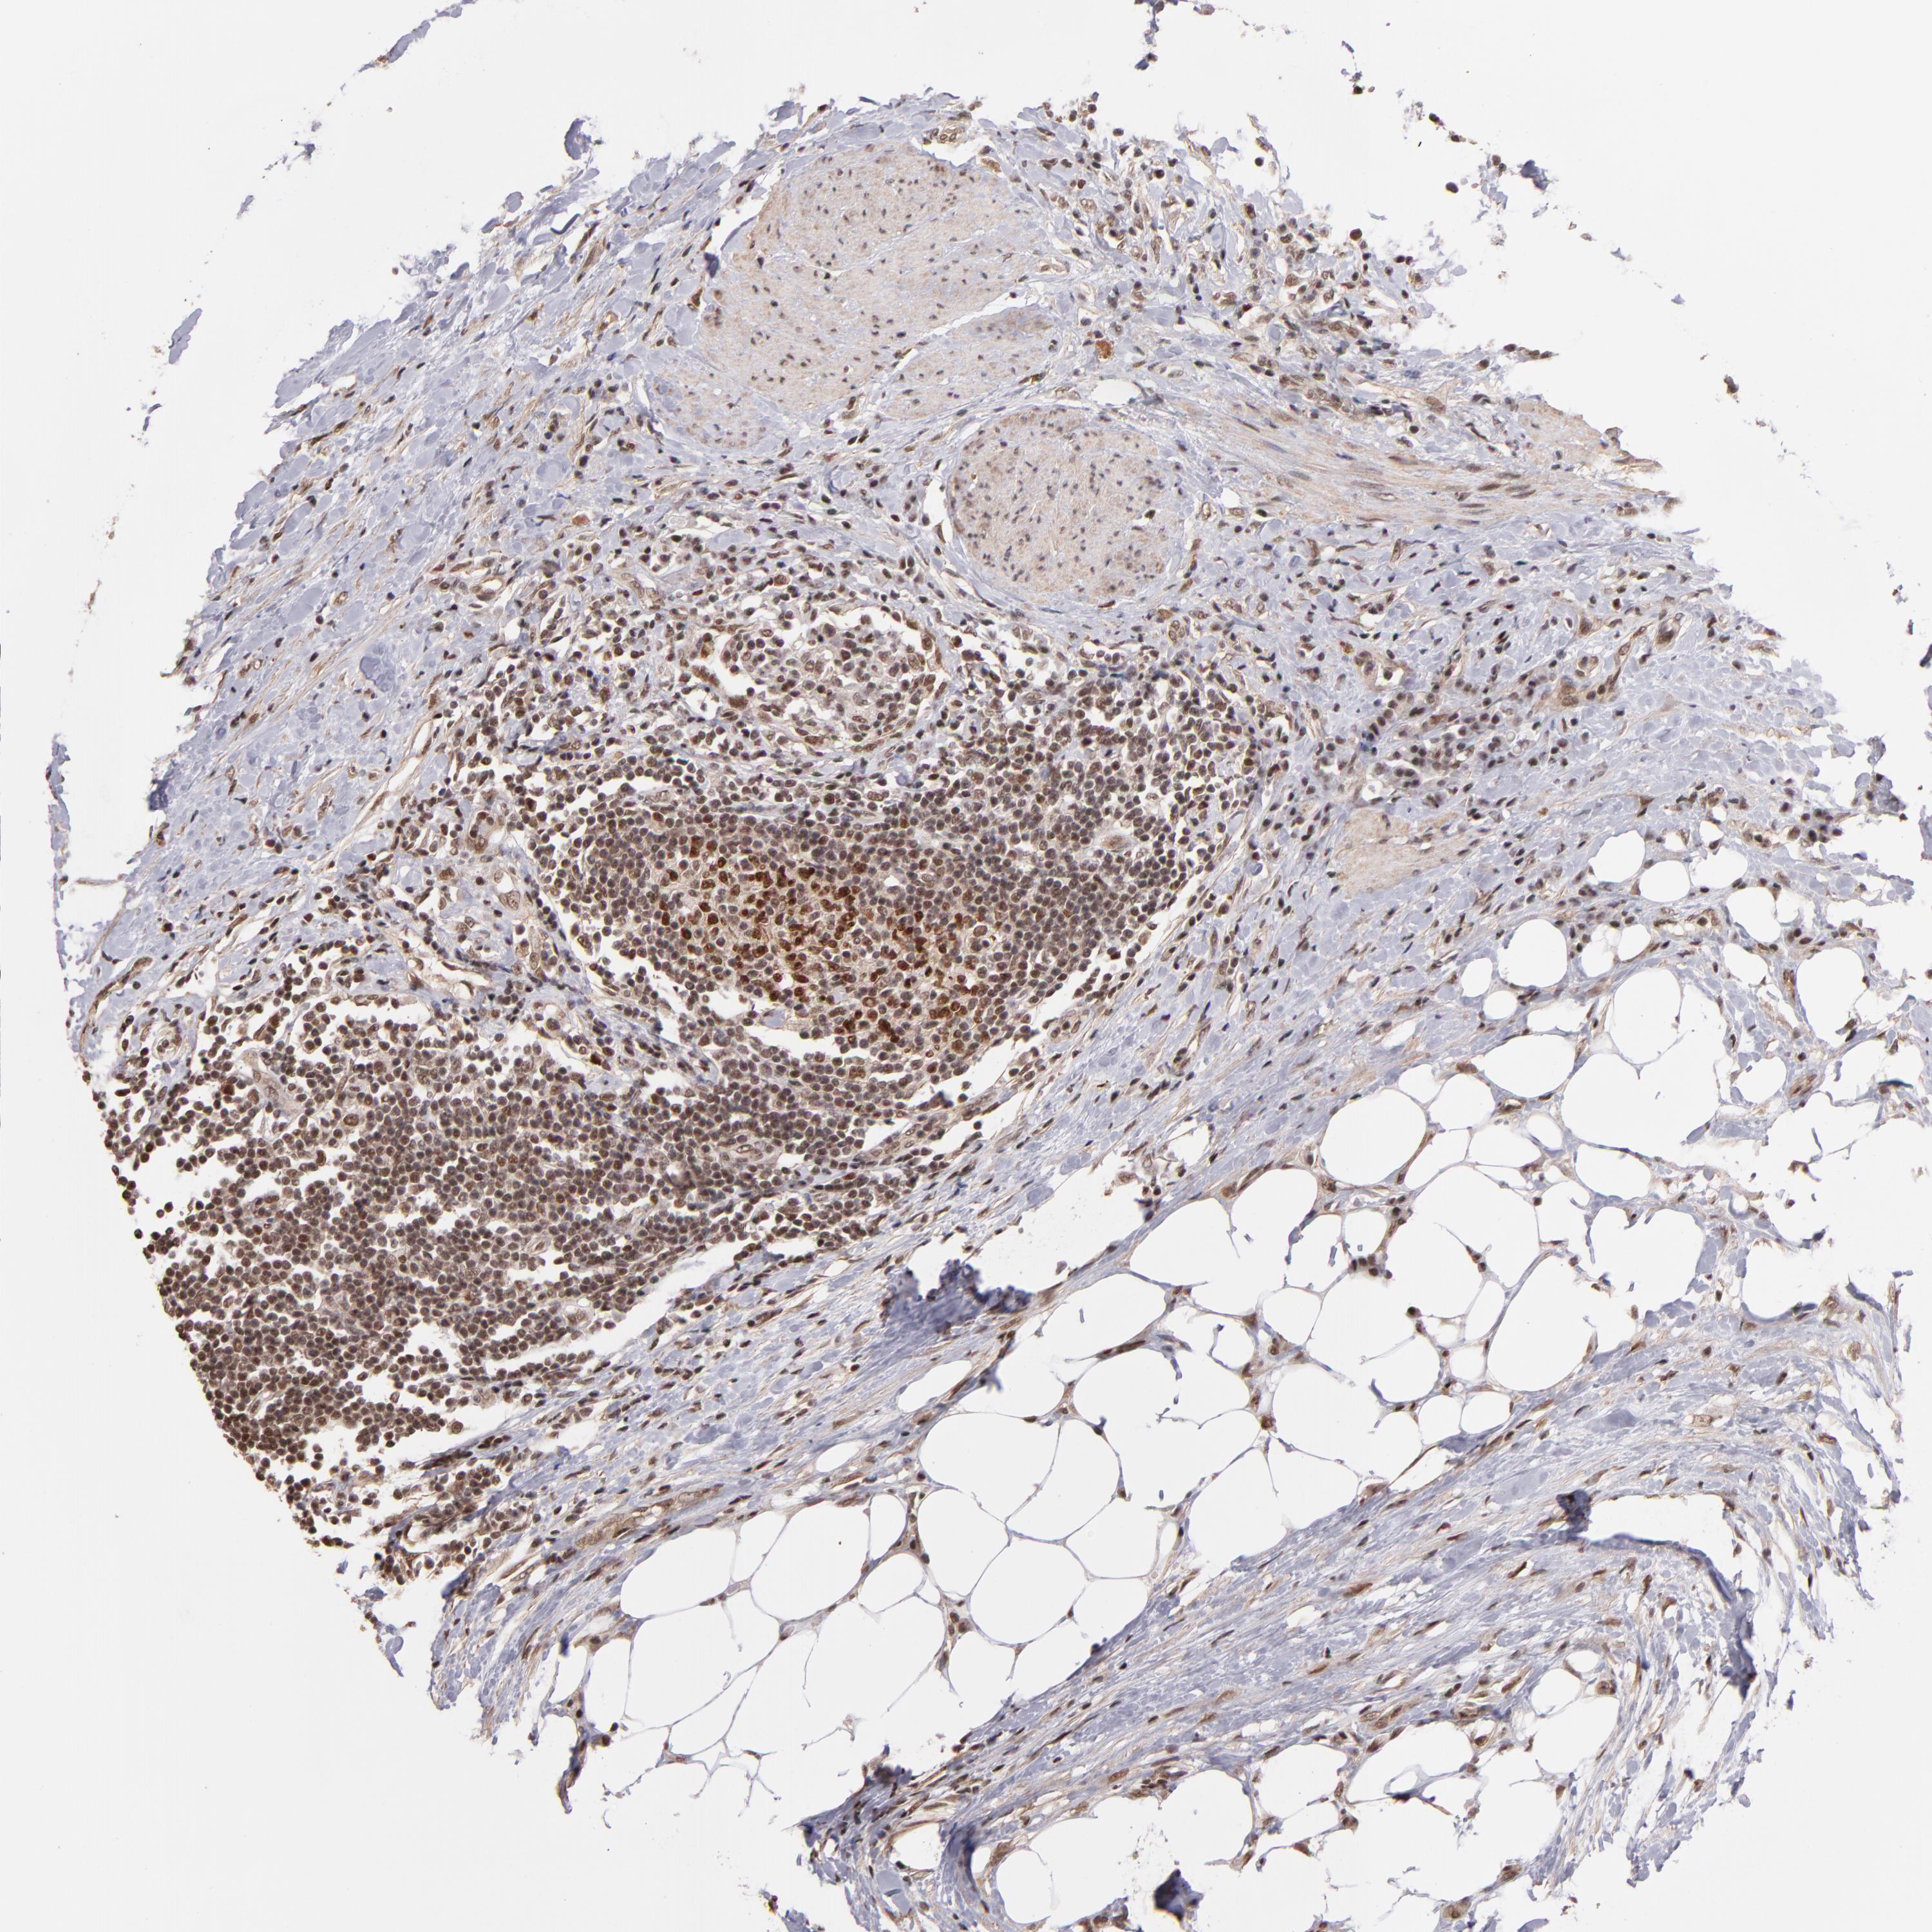

UROTHELIAL CANCER - Protein expressioni

A mouse-over function shows sample information and annotation data. Click on an image to view it in a full screen mode. Samples can be filtered based on level of antibody staining by selecting one or several of the following categories: high, medium, low and not detected. The assay and annotation is described here.

Note that samples used for immunohistochemistry by the Human Protein Atlas do not correspond to samples in the TCGA dataset.

Antibody stainingi

Antibody staining in the annotated cell types in the current human tissue is reported as not detected, low, medium, or high, based on conventional immunohistochemistry profiling in selected tissues. This score is based on the combination of the staining intensity and fraction of stained cells.

Each image is clickable and will lead to virtual microscopy that enables deeper exploration of all samples and also displays staining intensity scores, fraction scores and subcellular localization as well as patient and tissue information for each sample.

Antibody HPA001907

Antibody HPA002735

Antibody CAB010451

Antibody CAB080271

Staining

High

Medium

Low

Not detected

Intensity

Strong

Moderate

Weak

Negative

Quantity

>75%

75%-25%

<25%

None

Location

Nuclear

Cytoplasmic/membranous

Cytoplasmic/membranous,nuclear

Urothelial carcinoma, High grade

Urothelial carcinoma, Low grade

Adenocarcinoma, NOS